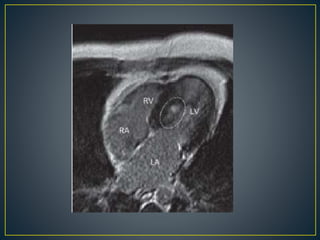

dysfunction

• Useful when echocardiography is questionable,

particularly with apical hypertrophy

• Cines loops typically show obstruction and velocity

mapping is useful in the assessment of peak velocities

• SAM of the mitral valve is clearly seen on cardiac MRI